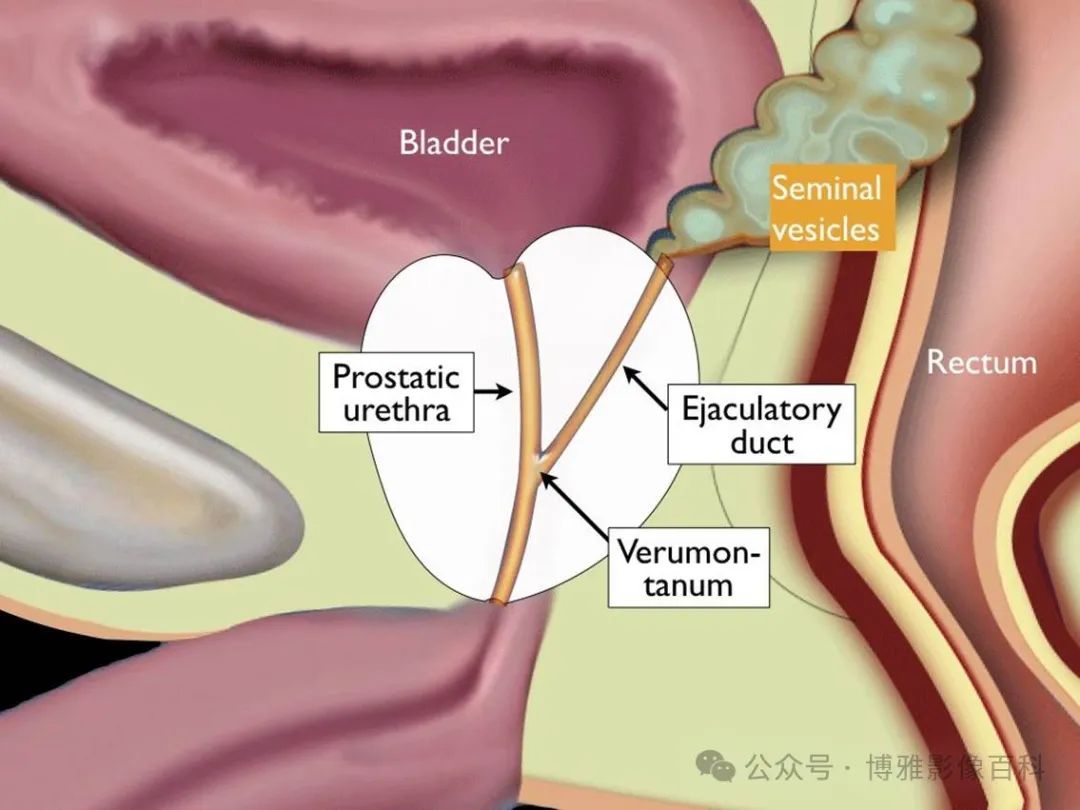

前列腺分区解剖学

扇区解剖

MR 解剖学